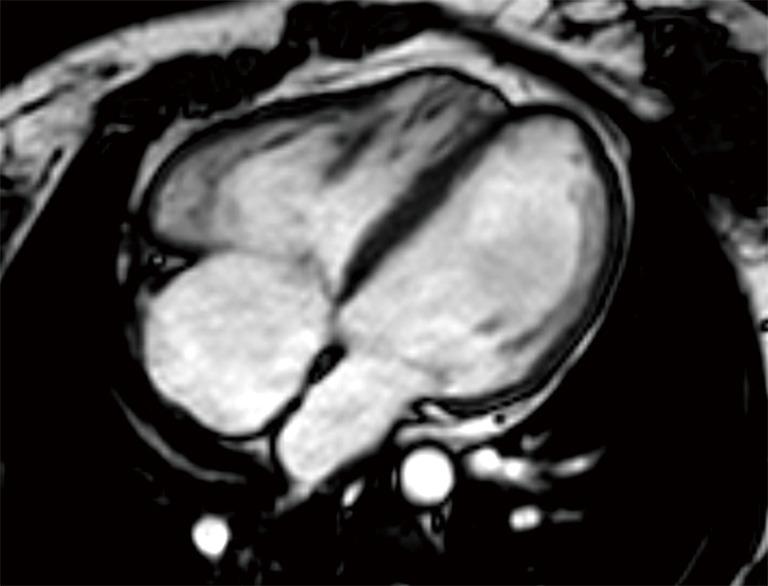

Thanks to advances in pediatric cardiology, most infants with tetralogy of Fallot (TOF) now survive into adulthood. This relatively new population of adult patients may face long-term complications, including pulmonary regurgitation (PR), right ventricular (RV) tract obstruction, residual shunts, RV dysfunction, and arrythmias. They will often need to undergo pulmonary valve (PV) replacement and other invasive re-interventions. However, the optimal timing for these procedures is challenging, largely due to the complexity of evaluating RV volume and function. The options for the follow-up of these patients have rapidly evolved from an angiography-based approach to the surge of advanced imaging techniques, mainly echocardiography, cardiac magnetic resonance (CMR), and computer tomography (CT). In this review, we outline the indications, strengths and limitations of these modalities in the adult TOF population.